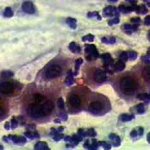

Πινακοθήκη κυτταρολογικών ευρημάτων ΙΙΙ

Οι πινακοθήκες κυτταρολογικών ευρημάτων, έχουν σαν στόχο να εμπλουτίσουν την κυτταρολογική εμπειρία σπουδαστών και ειδικευομένων, όπως ένας άτλαντας.

Παρουησιάζονται λοιπόν τυχαία ευρήματα, από το καθημερινό γυναικολογικό ιατρείο.